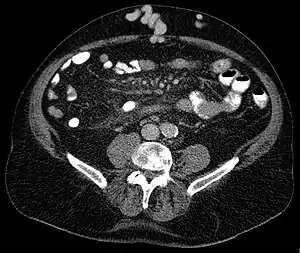

| Axial CT showing portosystemic collateral circulation via the umbilical vein: caput medusae in liver cirrhosis | |